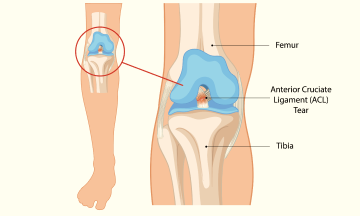

Ligament injuries, especially to the

Knee ligament injuries are common

If you've been around athletes,